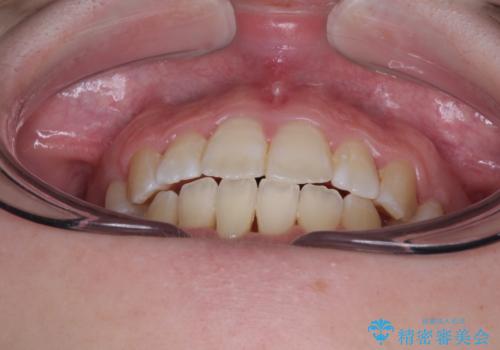

舌の突出癖を改善するためのトレーニングをしっかりと行っていただいたことで、比較的スムーズに治療を進めることができました。

口元の突出感もしっかりと改善することができました。